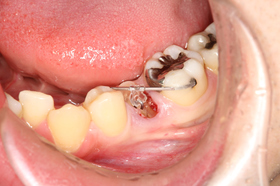

この患者さんも、クラウン(被せもの)の脱離を放置してしまい、どうにかならないかということで来院されました。

レントゲンを撮影すると、虫歯がかなり進行し、骨縁下(周囲の骨辺縁より下方)にまで及んでいるのが確認できました。

まず、歯にフックを装着し、フックと周囲の歯に維持を求めたバーにゴムを掛け牽引します。

すると、右下の写真のように歯が挺出し、今まで歯肉の下にあって見えなかった歯の部分が確認できるようになります。

頬側(外側)と舌側(内側)の歯が大分出てきています。